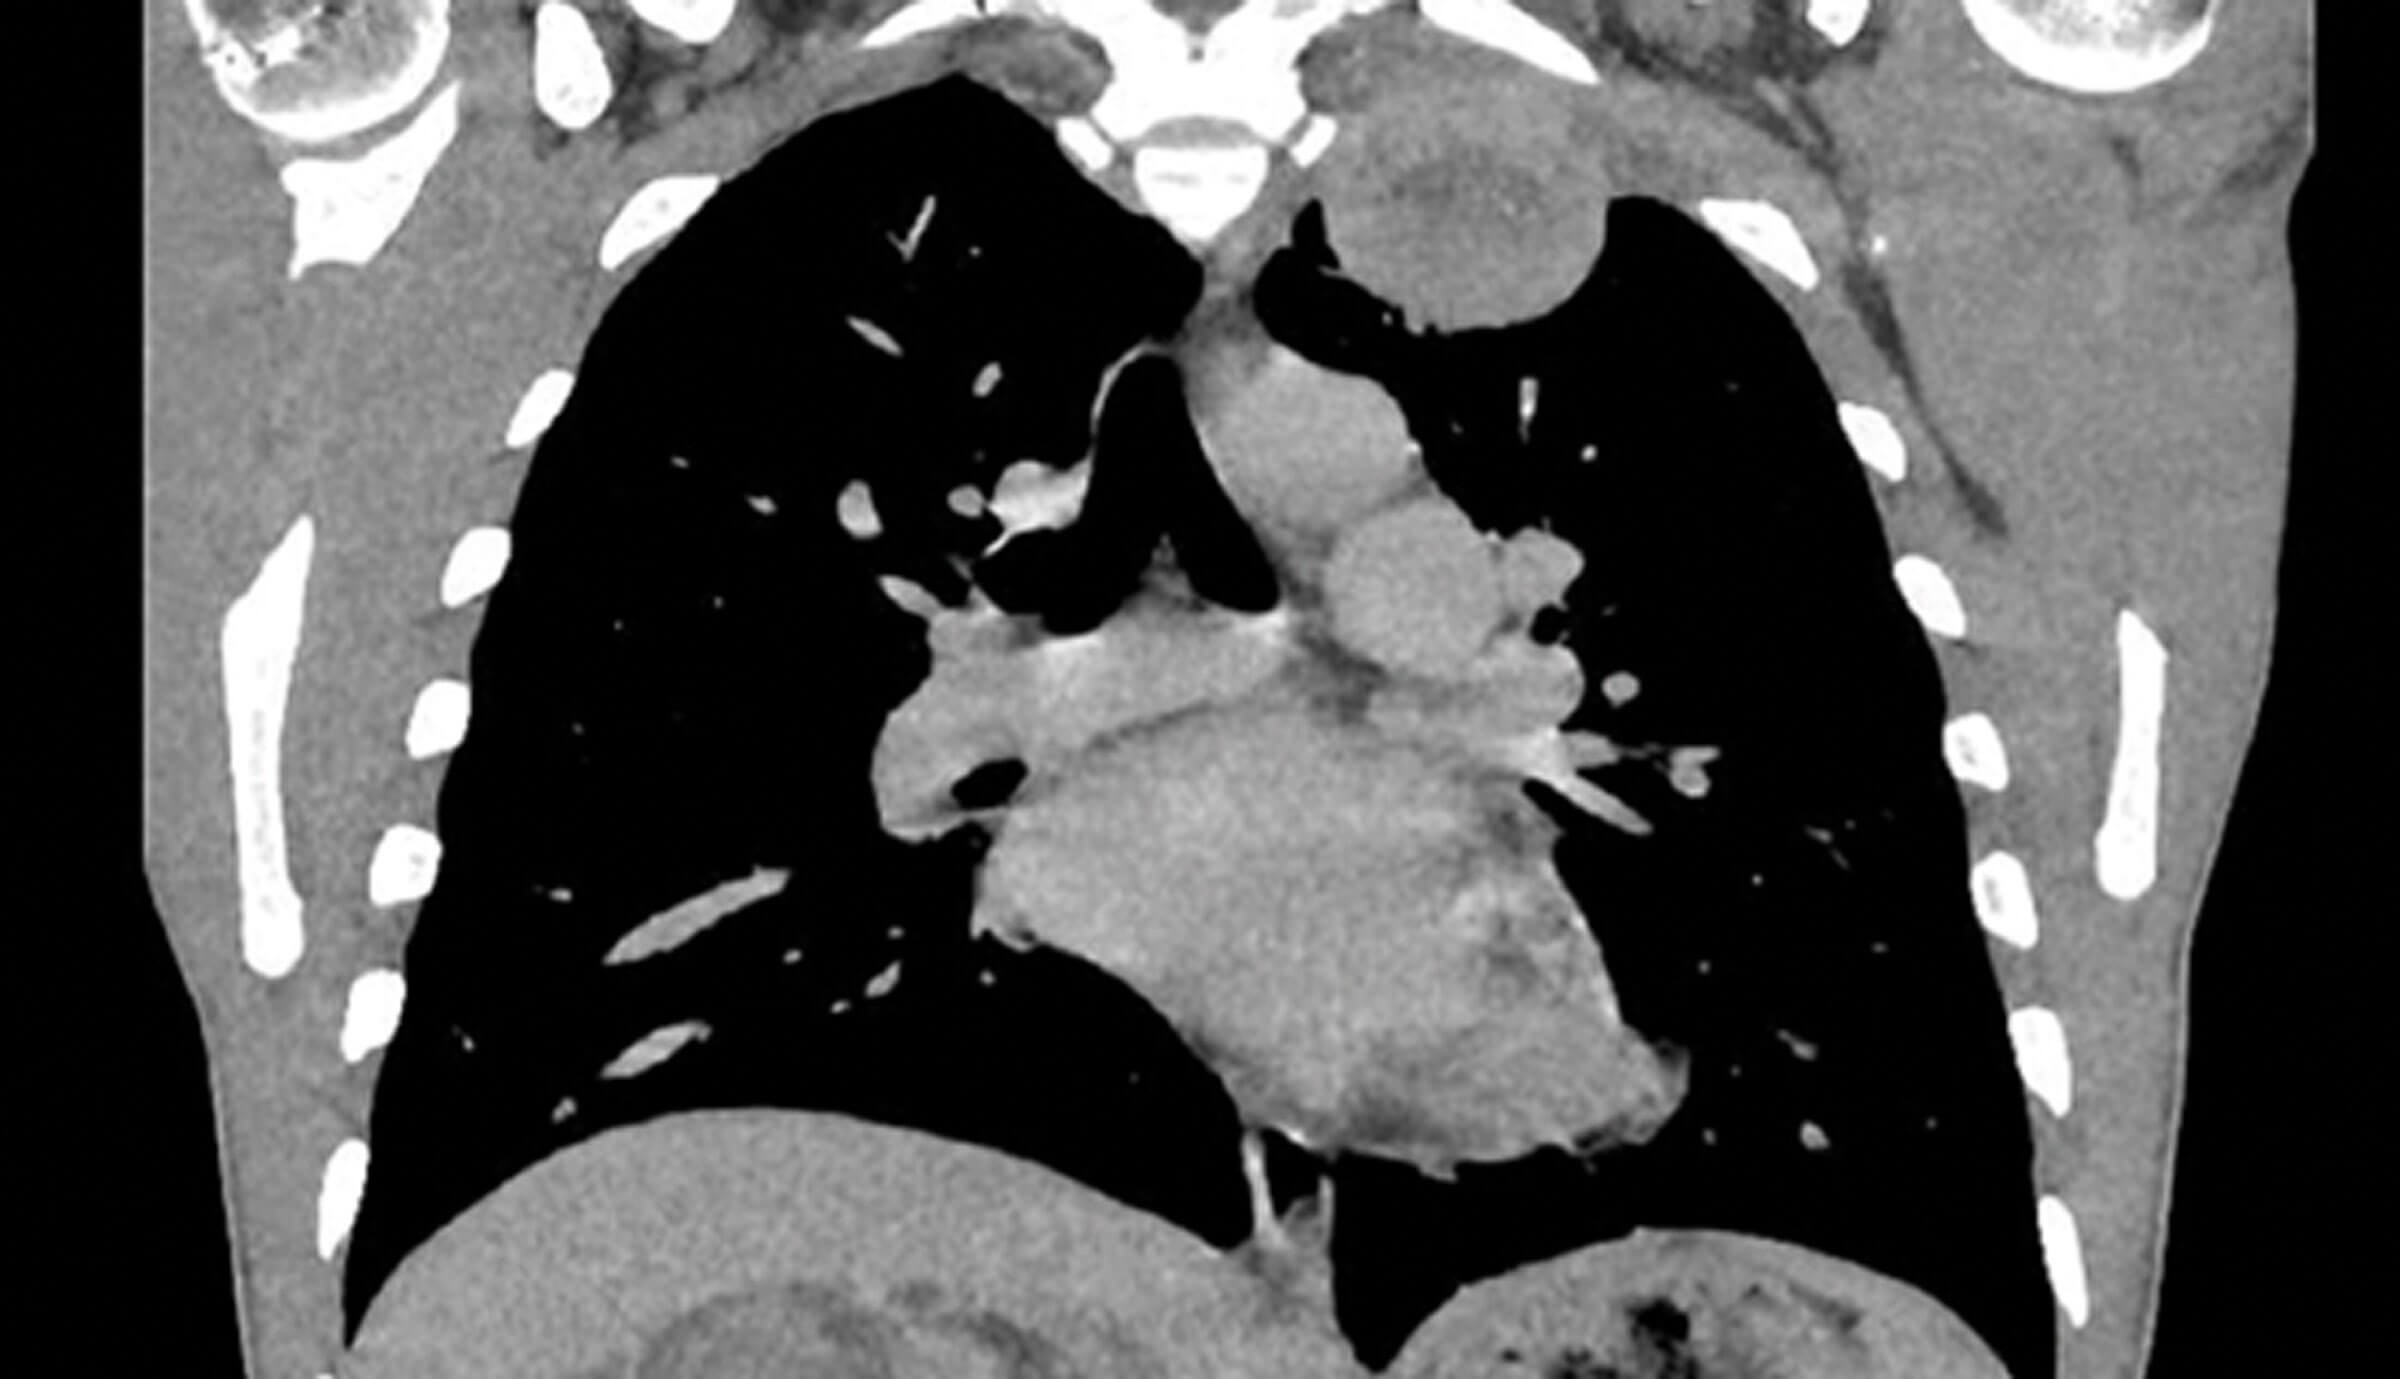

Figure 4.

1. Figure 3 is a coronal section of an arterial phase CT and demonstrates a large, heterogenous, solid, right tumour, which extends beyond Gerota’s fascia. Figure 4 is a coronal section of a thoracic CT demonstrating a left superior thoracic metastasis. These images demonstrate RCC with thoracic metastasis.